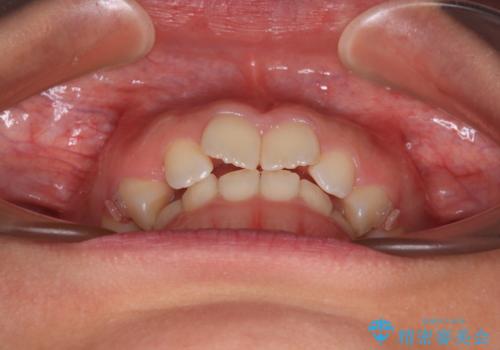

- 上の前歯が前方に飛び出していることを気にして来院された患者様です。

奥歯の咬み合わせをチェックすると、上顎歯列が相対的に前方に位置しているため、補助装置を用いて上顎歯列を確実に後方に移動させ、インビザラインで歯列を整えて行くこととしました。